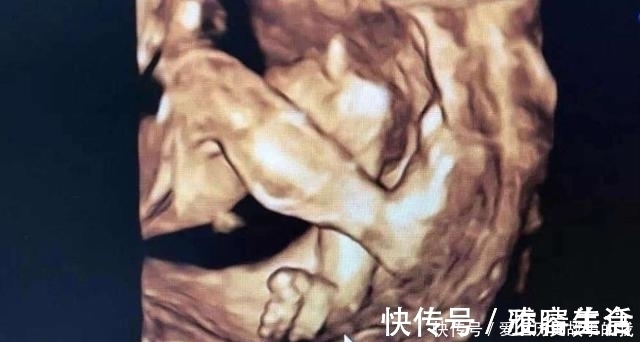

四维检查是对胎儿的各项器官进行排畸筛查,医生通过彩超仪器来观察胎儿的发育情况、胎盘、羊水等,还可以打印出比较清晰的胎儿面部图片,孕妈可以看到腹中孩子的大致长相。很多宝爸宝妈第一次看到宝宝如此清晰的照片,很激动,也顾不上看产检单上的其他数据,就只盯着照片看。其实,四维产检单出来之后,除了看宝宝的照片,其他数据一样要仔细看看。

四维彩超是可以比较清晰的看到孩子的四肢和颜面部的发育情况的,如果孩子有兔唇四肢畸形是可以发现的。